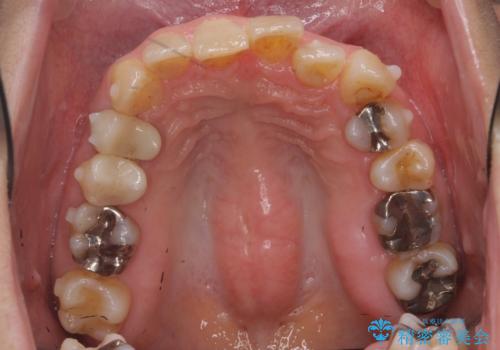

かみ合わせが深く、上の歯が咬みこんで下の歯にワイヤーがつけられない状態で、ワイヤー矯正はかなり難しい状態でした。

反対咬合や、すれ違い咬合もあり、大変難しいケースでしたが治療することができました。

かみ合わせが深い方はもともとかみしめが強く、マウスピース矯正を長期にすると、奥歯が咬まなくなってくる症状が強くなります。

今回もそういった状態になったのを、装着時間や歯の移動を工夫する形で治療しました。